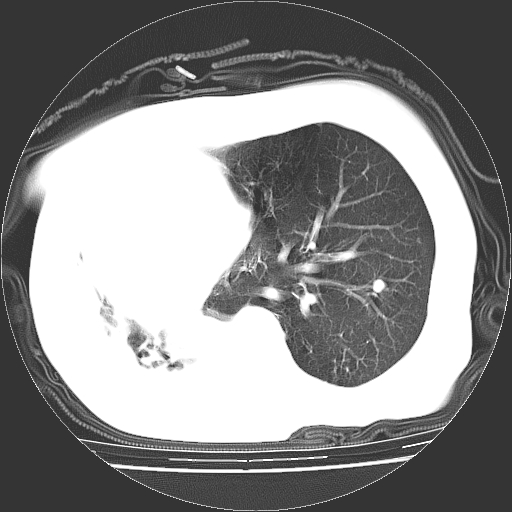

女,72岁,咳嗽、憋气一周,十年前曾患肺结核及胸膜结核。

右侧毁损肺,右侧纵隔疝

右侧毁损肺,右侧纵隔疝,左肺代偿!

右侧肺硬变,左肺代偿气肿。

1.右侧损毁肺伴胸膜钙化,2.左肺小结节灶,良性可能大,注意复查。3.肝脏左叶囊肿。4.先天性一侧肺不发育待出外(右侧胸廓无明显塌陷)。对比原片应该非常有帮助。

右侧肺毁损,左肺代偿性肺气肿,纵隔疝。